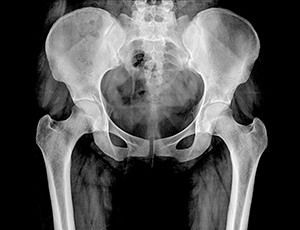

Рентген костей таза

Таз представляет собой часть скелета, которая расположена в основании позвоночного столба. Он не только является опорой для внутренних органов, но и обеспечивает фиксацию к туловищу ног. Именно поэтому его здоровье играет немаловажную роль, а рентген костей таза является неотъемлемой составляющей диагностики при заболеваниях и травмах этой области.

Что показывает рентген костей таза?

Расшифровка полученных результатов требует не только чётких снимков, но и соответствующих знаний у врача. Это обусловлено тем, что однотипные изменения имеют различную трактовку. Именно поэтому в процессе нужно учитывать анамнез и жалобы пациента: каждое заболевание или аномалия имеют определённые клинические проявления. Так:

• Заметные на снимке смещения в тазобедренном суставе сигнализируют о его вывихе;

• Аномалии строения головки кости бедра и вертлюжной впадины — признаки дисплазии;

• Сужение суставной щели и наличие остеофитов говорят о таком дегенеративно-дистрофическом заболевании, как остеоартроз;

• Затемнения — признак злокачественных новообразований, тени — метастатические очаги;

• Обломки костей подтверждают подозрения о переломе;

• Хорошо заметная регенерация костных структур является симптомом асептического некроза.